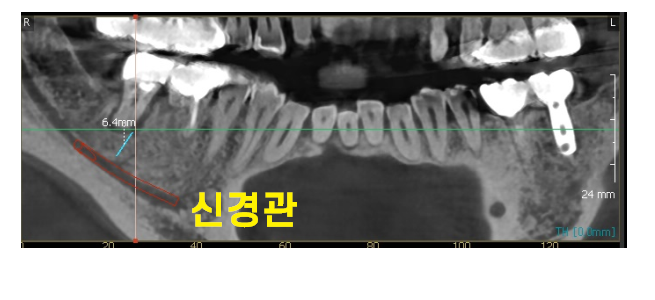

또한 ct에서 6.4mm 보이시죠~?

신경관과 치아 뿌리 사이 간격이 6mm라는 뜻입니다.

어금니 임플란트는 최소 8-10mm를 식립하는데

잇몸뼈를 녹일 수록 위험 부담도 높아지는거죠~

물론 네비게이션 임플란트 기술을 사용하면

최적의 식립 위치를 확인할 수 있기야 하지만

신경관과 가까워 신경손상 가능성이 있다~